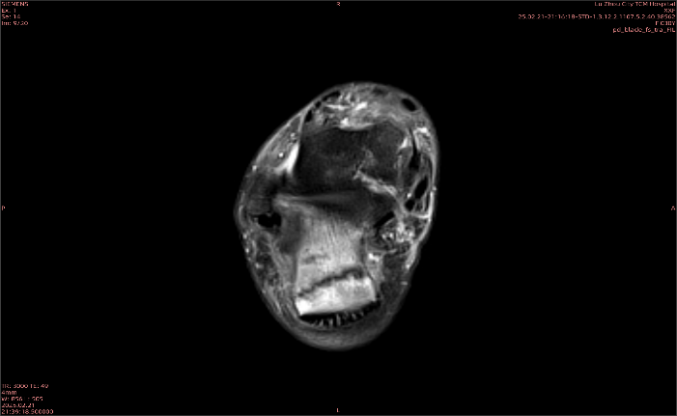

舉例圖像

圖2

專業(yè)解釋看不懂沒關(guān)系,大家看圖1和圖2就可以了,這是同一個患者跟骨的磁共振和CT圖像,圖1的紅色箭頭指示的黑線就是磁共振圖像顯示的骨折線,一目了然。而對比圖2的CT圖像上并未顯示異常。